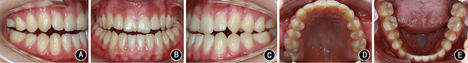

向患者详细阐述手术提前方案与传统术前正畸方案的优缺点及治疗风险后,患者自愿接受手术提前方案并签署知情同意书。术前拔除

残根、

阻生智齿。正畸初始弓丝为0.356 mm(0.014英寸)镍钛圆丝,术前弓丝为0.406 mm(0.016英寸)镍钛圆丝。并于

近中腭侧、

近中颊侧植入助攻型钛合金微螺钉作为骨性支抗,持续轻力(0.49~0.98 N)矫正

的颊向倾斜和

的舌向倾斜。经过2个月术前正畸即解除手术

干扰,转移咬合关系至

架,做模型外科操作,可获得稳定的术后咬合。转正颌外科手术,此患者虽然存在上颌后缩,但鼻唇角尚在能接受范围内,而鼻旁区凹陷更明显。因此提出两个手术方案:①双颌手术;②下颌单颌手术辅助鼻旁区植骨。患者及家属选择方案②行下颌双侧升支矢状劈开术、颏部成形术和鼻旁区植骨术,并于全麻下在上下颌前牙区及后牙区行种植体支抗植入术。术后2周去除颌间牵引,术后4周去除咬合板后行术后正畸。术中及术后于种植体支抗间行颌间牵引预防复发。术前正畸2个月,术后正畸13个月,总疗程16.5个月。

矫治后患者面型好,正面观患者面部对称,侧面直面型。上下颌牙列排列整齐,上前牙未发生明显唇向倾斜,下前牙去代偿。磨牙中性关系,前牙覆

覆盖正常。

过小牙修复间隙预备,维持

修复间隙。全口曲面体层X线片示牙根排列基本平行。患者对治疗早期即解决主诉感到满意,术后正畸阶段患者因妊娠而放弃前牙精细调整。